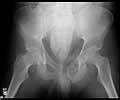

25 yo brittle diabetic, became hypoglycemic and passed out on his motorcycle. Sustained bilateral lateral Hoffa fractures with associated LCL injury on the right and right distal radius fracture. I have questions regarding his pelvic ring/acetabular fracture on the left. Appears to be a very low posterior column fracture with associated posterior wall, marginal impaction. Superior and inferior rami fractures as well on the left giving him a floating segment of inf ramus/ischium/posterior column, but no detectable posterior ring injury. Should the posterior column/posterior wall fracture be addressed surgically because of the marginal impaction? Or is this fracture low enough to be treated non-operatively? I appreciate the input.

I believe the more serious component of the acetabular fracture to be the large (almost 50%) impacted, comminuted zone of the posterior wall. In several series, including the one I reported at the AAOS in 2002 in Dallas of 100 acetabular fractures with posterior wall involvement, all repaired by a single surgeon (Kyle Dickson), those with posterior wall impaction did significantly worse than those without. Nevertheless, the large area of involvement, as well as a joint designed for very low tolerances of "out of round", would indicate that the best chance for avoiding early degenerative changes would be an anatomic repair.

It's an interesting case. The plain films show the impaction, but most of the joint looks pretty good. The CT cuts look awful, though.

The impaction is so big I don't think I would ignore it. It IS down low, but it takes up almost the whole southern hemisphere of his joint.